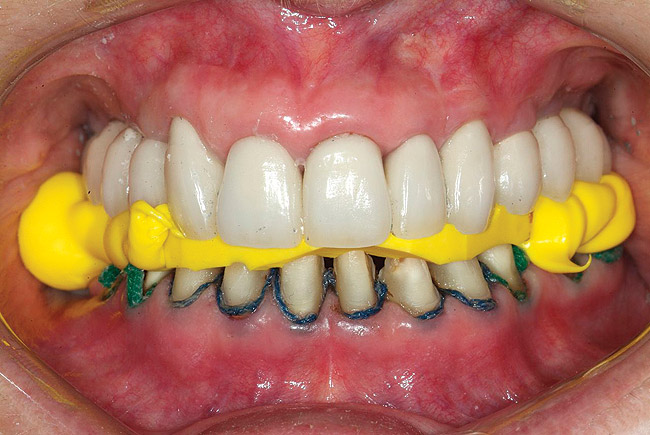

Figure 4  Interocclusal registration made at the approximate OVD for rehabilitation.

Figure 4

Figure 5  Accurate casts mounted at arbitrary OVD.

Figure 5